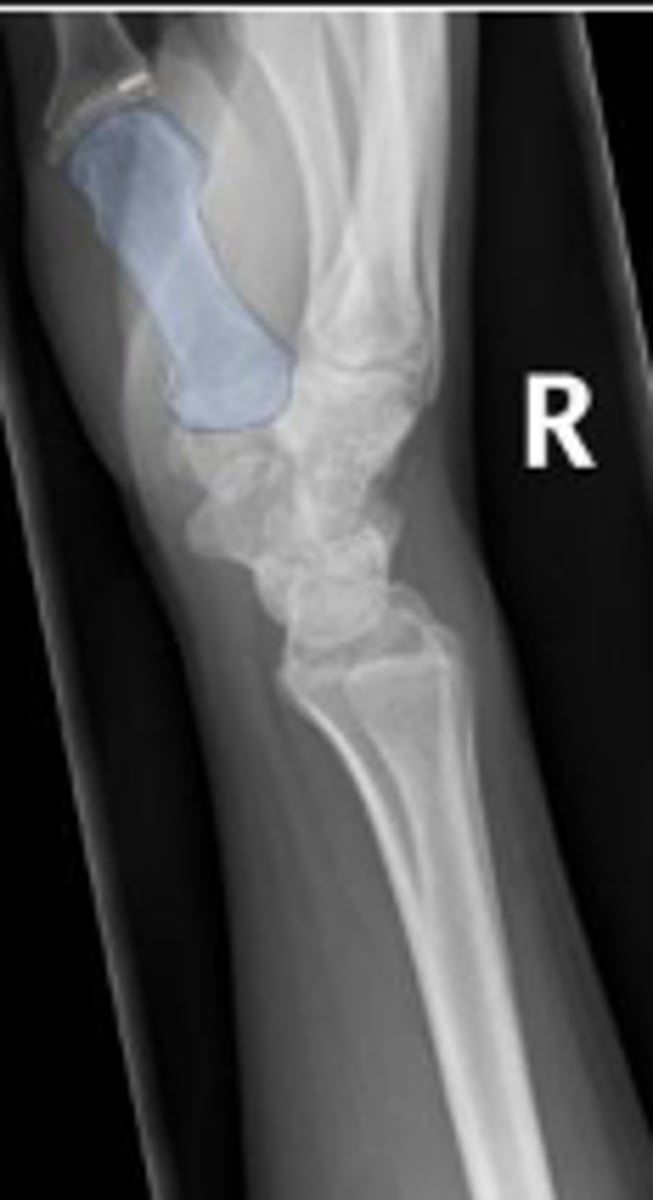

Left lateral wrist

What is the name of the radiographic view?

Volar margin of the left radius

What is the arrow pointing to?

Dorsal margin of the left ulna